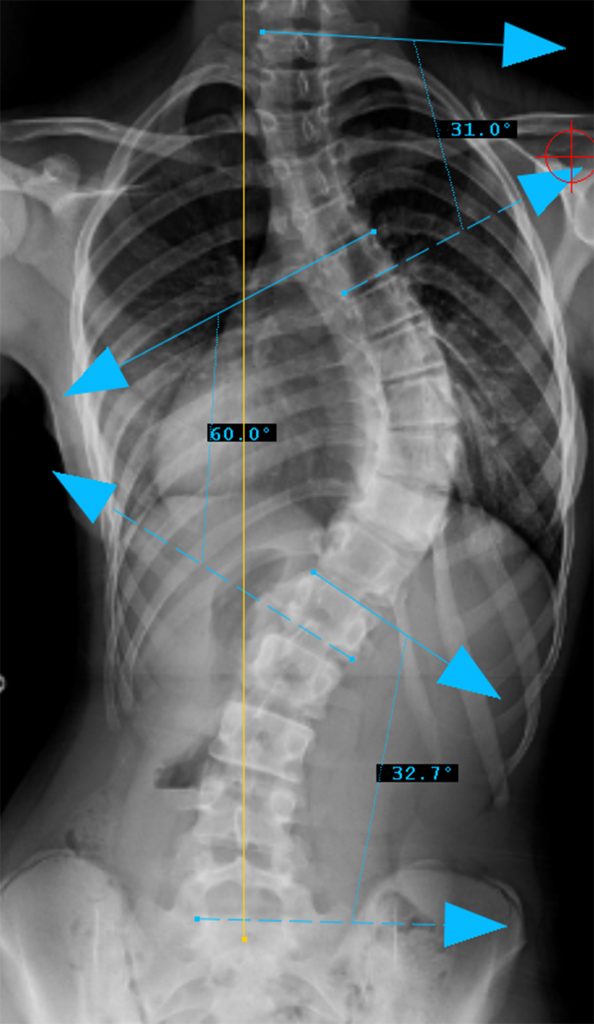

Preop PA View